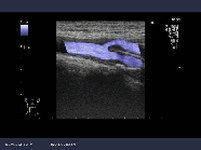

頚動脈エコー

超音波検査装置 (HITACHI ARIETTA 60)

超音波を使って頚動脈の状態を調べる検査です.血管の壁の厚さ(サビのつき具合)を測定し動脈硬化の程度を判定します.頚動脈の行き着く先は

『脳』です.すなわち頚動脈の動脈硬化性病変は脳梗塞の大きなリスクになるのです.頚動脈の動脈硬化の程度は全身の動脈硬化の進行具合の指標に

もなります.また,高血圧,糖尿病,高脂血症とも密接に関連し,治療の良否の判断にも利用されます.検査に要する時間は,10~20分位で,

特に予約は必要ありません.痛みや危険性は全くない安全な検査です.

●保険適応の検査であり,費用は3割負担の方で,1650円,1割負担の方ですと550円位です.